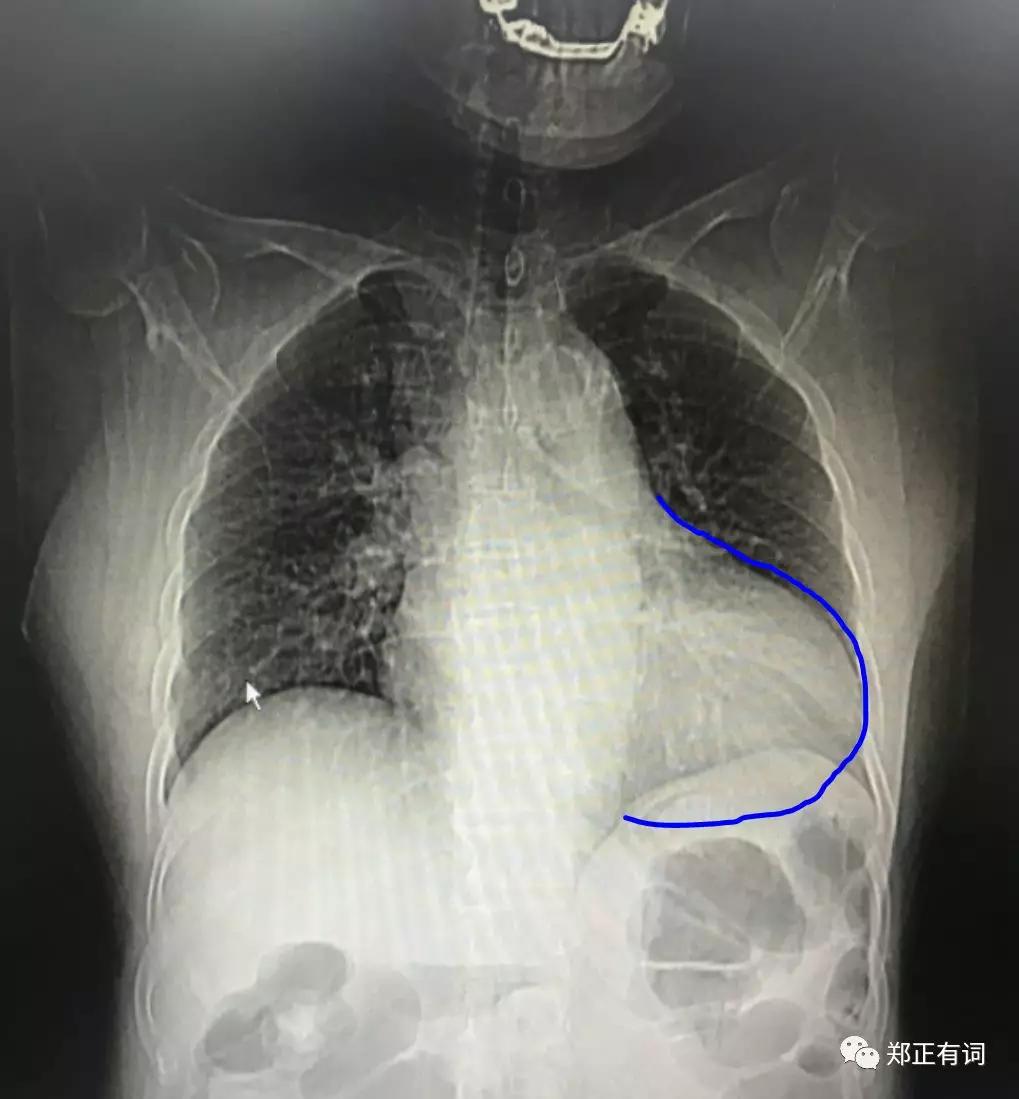

在术前检查过程中,我们发现患者的心胸比例异常,在平片上可见靴形心的典型影像学表现,而这正是高血压心脏病的典型表现。

而患者长年高血压病史(十余年)及密集的高血压家族史(多位直系亲属罹患),也进一步支持了这种判断。

因此,尽管其自诊断之日开始就积极口服多联降压药控制血压,但有理由相信,患者应该在更早的时间内就发生了高血压,只是自己不知道罢了,而心脏也在这个漫长的过程中,发生了心肌重构,即左心室肥大,并产生了靴形心的典型表现。